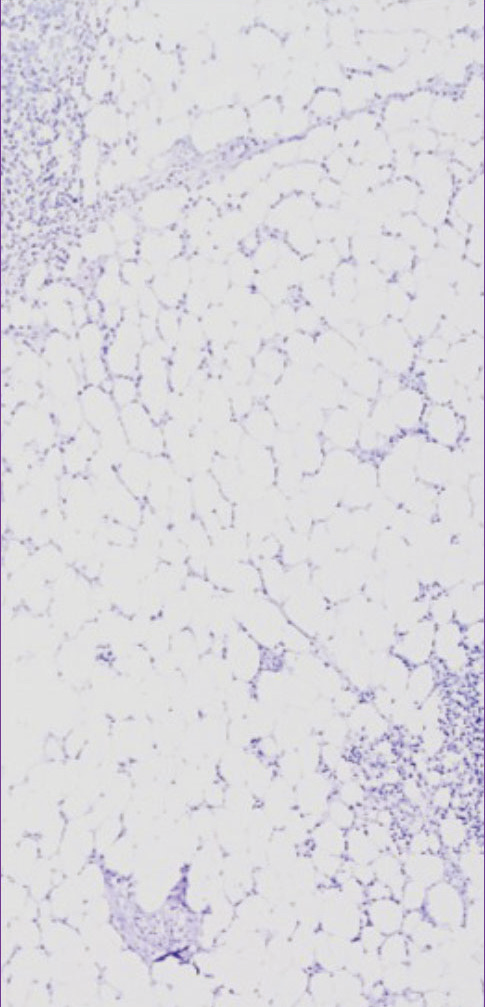

☝上图为:完成3轮TSA染色后的合成图像,每次染色完成后均使用VectaPlex™抗体洗脱试剂。 |

样本为扁桃体FFPE: 3种小鼠来源的一抗,分别为CD3 (红色), CD68 (绿色), AE1/AE3 (紫色), 蓝色为DAPI染色。使用Opal 3-Plex TSA试剂盒进行检测。 |